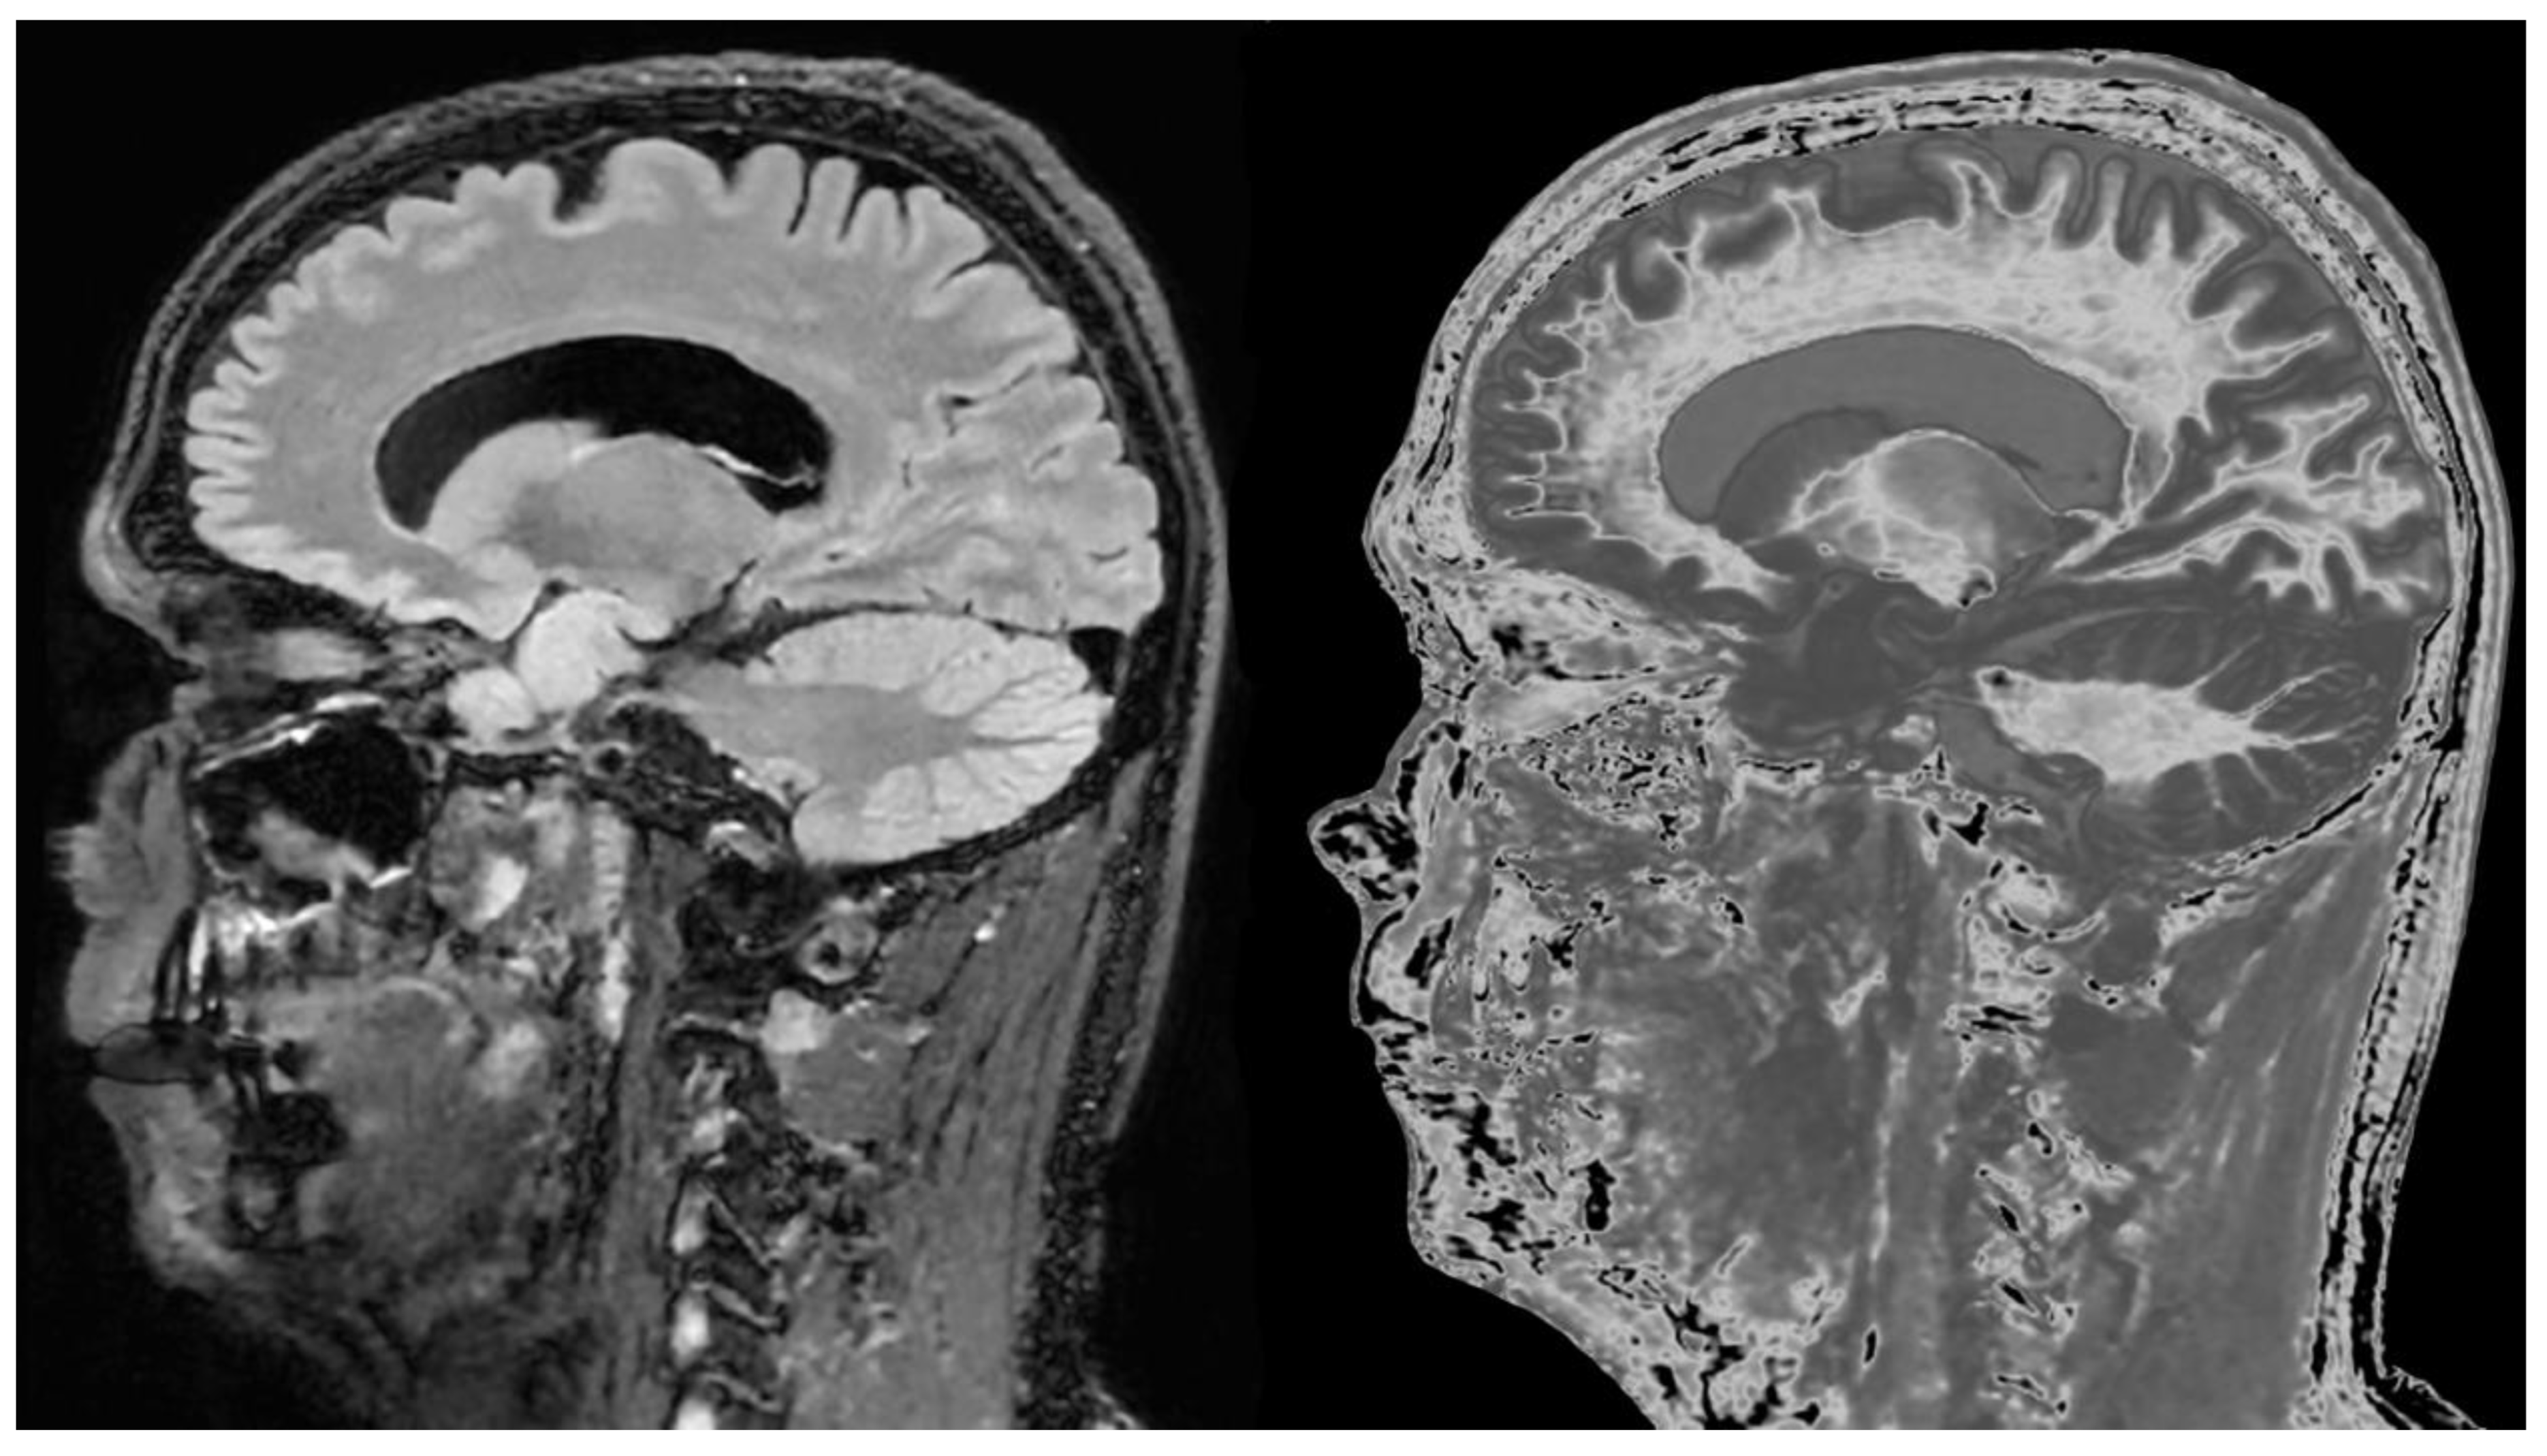

In addition to the whiteout sign, there may be loss of contrast in the gray matter of the thalamus due to an increase in T

1. This is manifest as a low contrast appearance between the medial and lateral thalamus (

Figure 12A) (arrows) (a grayout sign). After remission normal high gray white matter contrast is restored (

Figure 12B) (arrows). Contrast between the lateral thalamus (arrows) and the posterior limb of the internal capsule (PLIC) is low in (

Figure 12A) but very high in (

Figure 12B). The low contrast between the thalamus and the PLIC in (A) results from a reduction in signal in the gray matter of the lateral thalamus due to an increase in its T

1 in the hD as well as an increase in signal in the white matter of the PLIC due to an increase in its T

1 in the mD. This is reversed in (

Figure 12B) where the normal high contrast boundary is restored.

Figure 13A shows a normal control with obvious contrast between the heads of the caudate nuclei and the adjacent CSF as well as between the cortex and CSF.

Figure 13B shows a patient with mTBI who has a whiteout sign. There are grayout signs in the thalamus and putamen. In addition, contrast is lost between the heads of the caudate nuclei and CSF as well as between cortex and CSF which appear isointense. These are grayout signs. Thus, the patient has a combination of whiteout and grayout signs.

There may also be gray matter changes elsewhere in mTBI. The normal red nuclei have relatively short T

1s resulting in their normal signal being mid-gray in the mD (arrows) (

Figure 14A). They shows a higher signal due to increase in T

1 in a case of mTBI (arrows) (

Figure 14B).

Figure 12.

18-year-old patient with mTBI 21h (A) and 64h (B) post injury imaged with the same narrow mD dSIR (T1-BLAIR) sequence. In (A) the patient shows a whiteout sign (grade 4 out of 5) with high signal in most of the white matter in the cerebral hemispheres except for the anterior and posterior central corpus callosum. The posterior limb of the internal capsule is high signal. The thalami show low internal contrast from medial to lateral (arrows on lateral margins of the thalami). There is also low external contrast between the lateral margins of the thalami and the adjacent posterior limbs of the internal capsule.On the follow up examination at 64h (B) the whiteout sign has resolved with low signal now in the white matter including the posterior limbs of the internal capsule (except for the corticospinal tracts). The thalami now show high internal contrast from medial to lateral (arrows on lateral margins of the thalamus) which is the normal appearance at this age. There is now also very high external contrast between the lateral margin of the thalamus and the adjacent posterior limb of the internal capsule. Image (A) shows the grayout sign which is a reduction in the high contrast between the medial and lateral gray matter of the thalamus. The high contrast is restored in (B). No abnormality was seen on the corresponding T2-FLAIR images obtained at both time points.

Figure 13.

Normal control (A) and patient with mTBI (B) showing a whiteout sign and grayout signs (narrow mD dSIR [T1-BLAIR] images). The normal control shows the heads of the caudate nuclei with higher signal than the adjacent CSF. Contrast is also seen between the cortex and CSF. In (B), the patient shows a whiteout sign. There are grayout signs in the thalami and putamina. In addition, contrast between the heads of the caudate nuclei and CSF is reduced and there is little or no contrast between cortex and CSF which are isointense. These are also grayout signs. No abnormality was seen on the T2-FLAIR images in the normal control or patient.